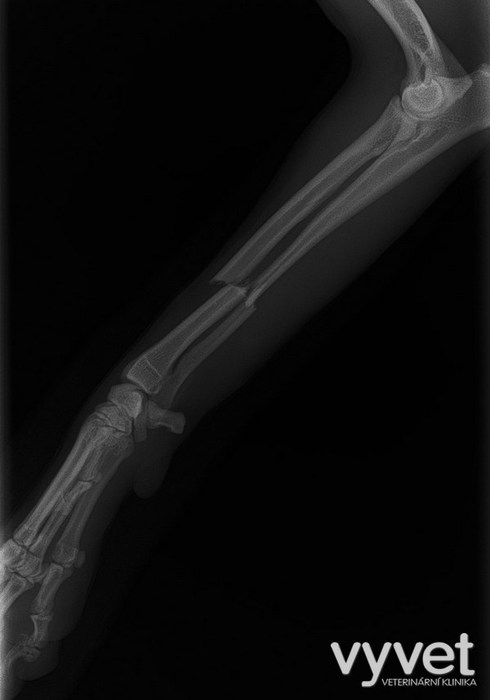

Nejčastějším problémem dlouhých kostí jsou zlomeniny (fraktury)

Rozdělujeme je do několika skupin podle charakteru, množství fragmentů, průběhu linie lomu, dislokace, stability atd.

Je mnoho popsaných metod fixací fraktur. Neinvazivní metodou je přikládání fixačních obvazů a kastů. Tento typ fixace však není ideální, protože nejsme schopni u zvířat zabezpečit dostatečně dlouhou dobu klidu pro srůst kosti. Ideální metodou je invazivnější přístup a to chirurgická repozice s následnou fixací osteosyntetickým materiálem.

Na našem pracovišti používáme zejména ploténky a hřeby.